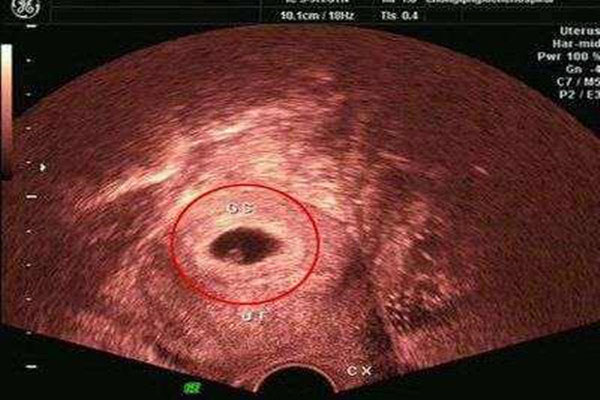

2个月的试管胚胎,面部基本像人了,做B超可见孕囊约占官腔1/2,胎宝宝形状及宝宝胎动清晰由此可见,并可看到卵黄囊,此时的小胎儿距离胎动还有好长的一段时间。